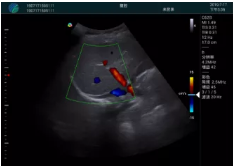

頸動(dòng)脈血流充盈飽滿,無外溢

肝內(nèi)血管顯示清晰,血流敏感無外溢

甲狀腺囊性結(jié)節(jié),囊壁鈣化,透聲好

甲狀腺囊性占位